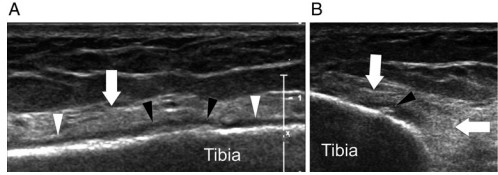

Estas imágenes se hicieron en un corredor de 28 años. Son un corte ecográfico longitudinal (A) y axial (B).

El periostio aparece engrosado, señalado con las puntas de flecha blancas, y muestra calcificaciones focales, indicadas por las puntas de flecha negras. También se aprecia una irregularidad focal de la cortical ósea y un edema hiperecoico en los tejidos blandos profundos, señalado con las flechas blancas.